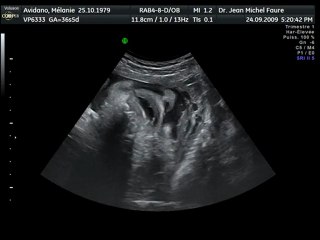

Echographie Souvenir 3D 4D chez Baby Live Montpellier